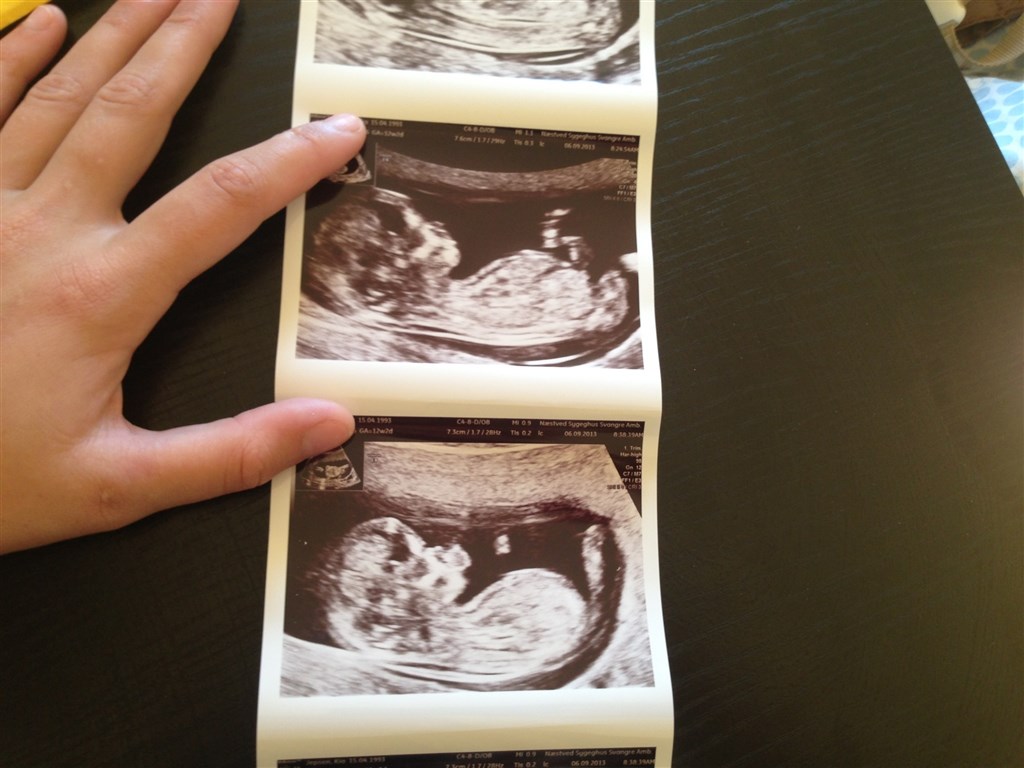

Vi skulle til NF scanning i dag, vi var både spændte men også rigtig nervøse! :-)

men alt gik godt, fik nogen rigtig fine tal, såsom nakkefolden blev målt til 1,3, og vores tal for kromosomfejl var 1:18269! :-) så det var jo helt fantastisk, blev rykket to dage frem også.

vi har fået billeder med hjem af lille'fisen og den gav os allerede fingeren, hvordan skal det ikke gå i teenage alderen? ;-) haha